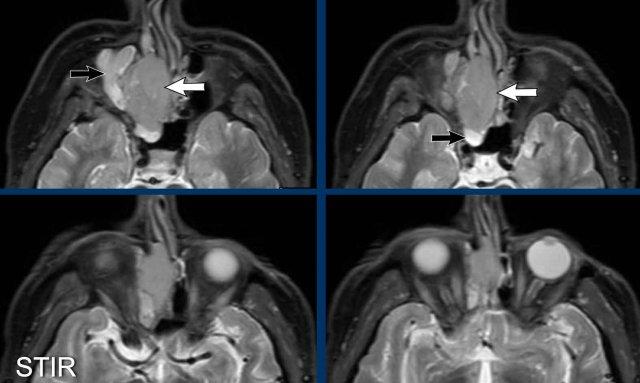

Tiếp tục với MRI…

Trên các hình ảnh STIR này, có thể thấy sự khác biệt về cường độ tín hiệu giữa xoang hàm và xoang sàng bị tắc nghẽn (mũi tên đen) và khối u (mũi tên trắng).

Ở bệnh nhân nang nhầy, toàn bộ tổn thương sẽ có cùng cường độ tín hiệu, khác với trường hợp này.

Trên hình ảnh khuếch tán, tổn thương có tín hiệu cao trên b1000.

Trên bản đồ ADC, tổn thương có tín hiệu rất thấp, thậm chí thấp hơn cả mô não, gợi ý tình trạng hạn chế khuếch tán rõ rệt.

Điều này có nghĩa là chúng ta đang đối mặt với một khối u tăng mật độ tế bào.

Đây là dấu hiệu cảnh báo thứ ba.

Trên CT, có thể có ấn tượng rằng khối u cũng xâm lấn xoang trán (mũi tên đen).

Tuy nhiên, trên MRI, chúng ta có thể thấy rõ ràng rằng xoang trán chỉ bị tắc nghẽn và có cường độ tín hiệu cao hơn (mũi tên trắng) so với khối u ở các xoang sàng (mũi tên vàng).

Kết luận cuối cùng là:

- Khối u ác tính ở hốc mũi phải với xâm lấn xoang sàng và xoang bướm.

- Không xâm lấn xoang trán và không xâm lấn nội sọ.

- Phá hủy thành trong xoang hàm và vách mũi.

Sinh thiết cho thấy ung thư biểu mô không biệt hóa vùng mũi xoang (SNUC), có tiên lượng rất xấu.

Bệnh nhân được điều trị bằng phẫu thuật cắt bỏ và xạ trị sau mổ, và thật bất ngờ, không có dấu hiệu tái phát sau bốn năm.